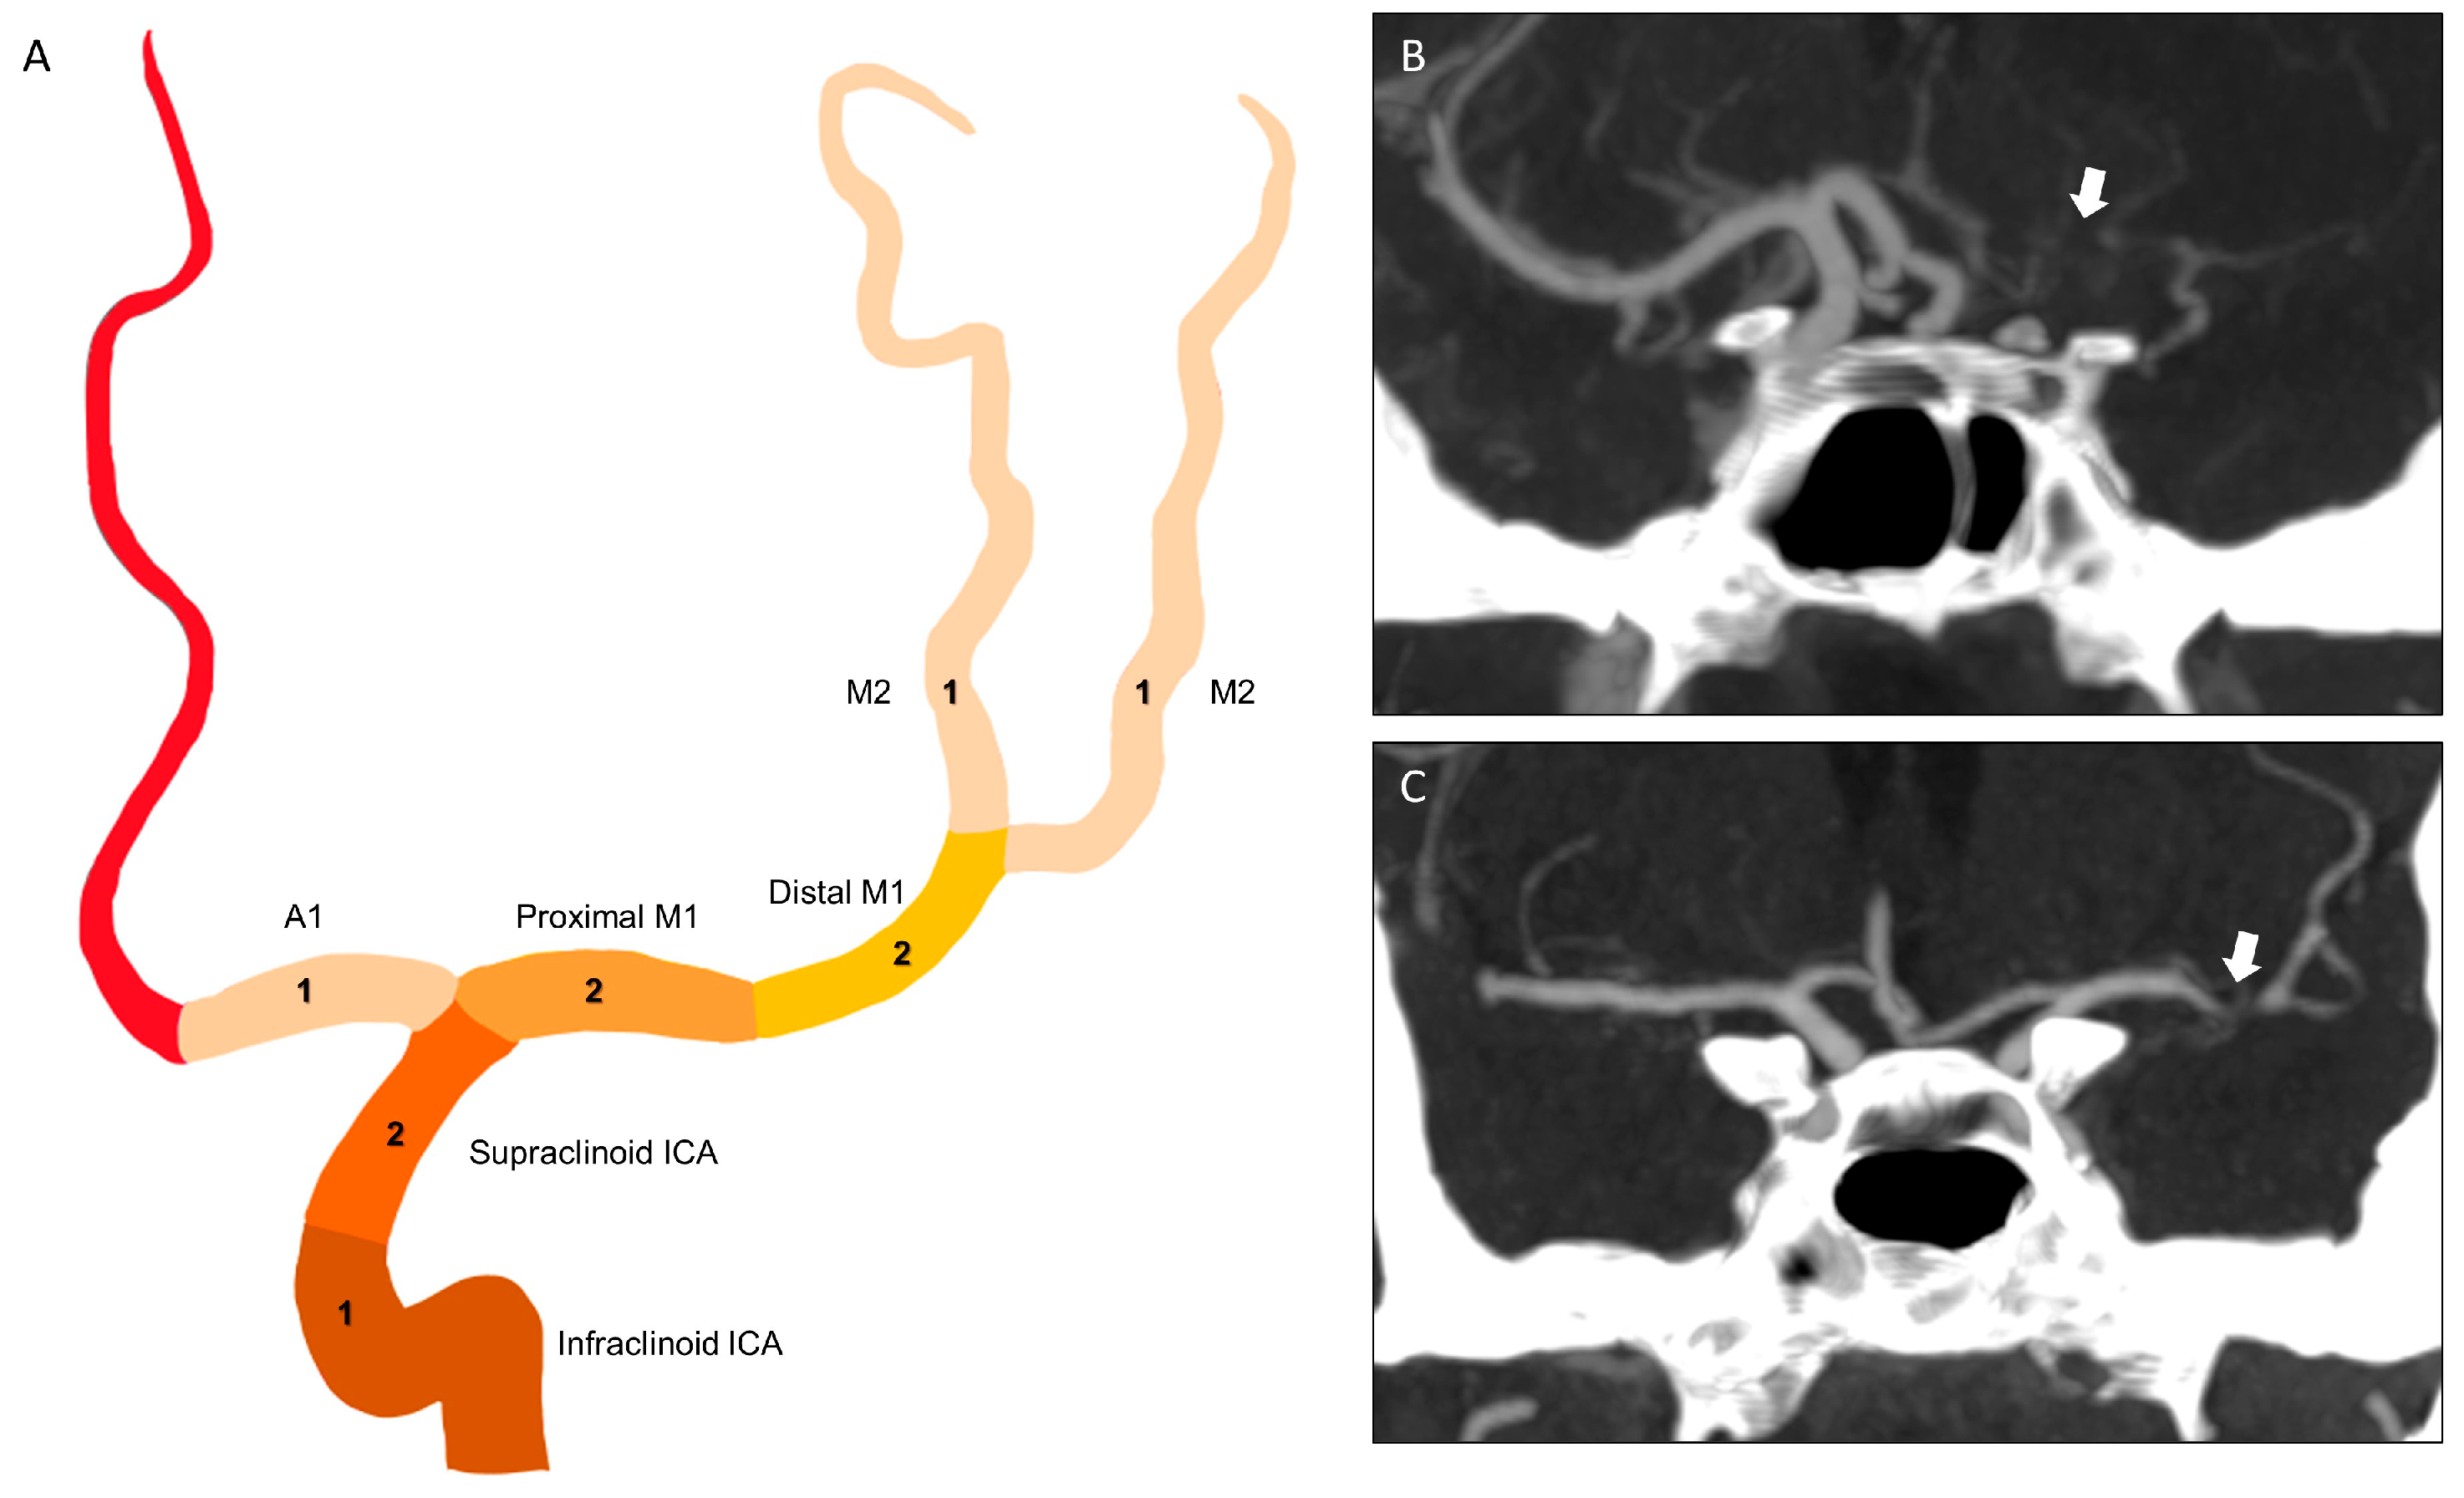

2.2. Imaging Protocol and Analyses